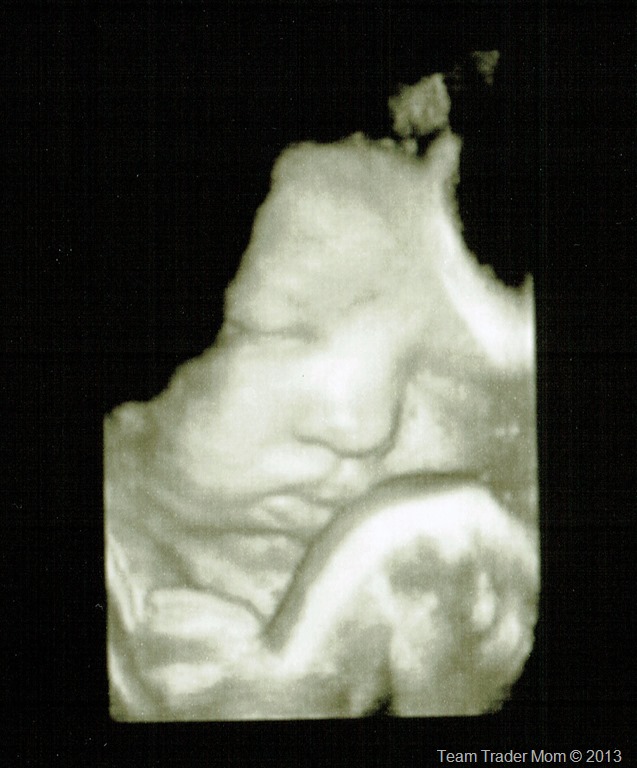

3D_39wks_4.4.13-3

3D of the baby’s face with an arm partially in front

The umbilical cord is wrapped twice around the baby’s neck.

When I first heard this, I panicked and thought we would need to do an emergency surgery or something but my doctor assured me that there’s nothing to worry about. This happens all the time, particularly in really active babies like TTB. There can sometimes be issues during a vaginal delivery if the cord starts to pull on the baby’s neck while it’s going through the birth canal but you just don’t know until it happens. And if it does, there are things they can do. Plus, there’s always a chance the baby could unwind itself as it moves around these last few days too.